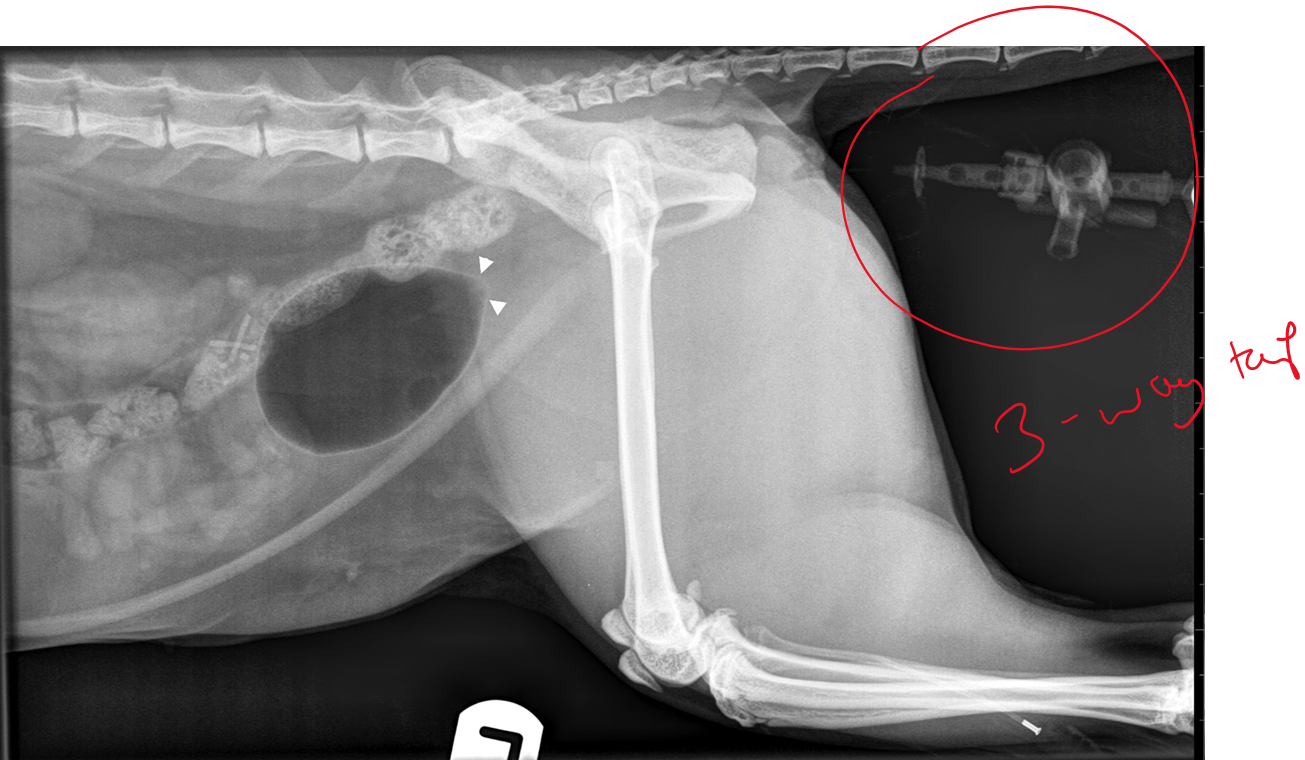

What is being shown in this radiograph and what are the possible causes?

Enlarged kidney —> increased soft tissue opacity in kidney

DDX = Cysts, haemorrage, abscess, neoplasia, granulomatous inflam, hydronephrosis

Metastasis of neoplasia (smaller circles)